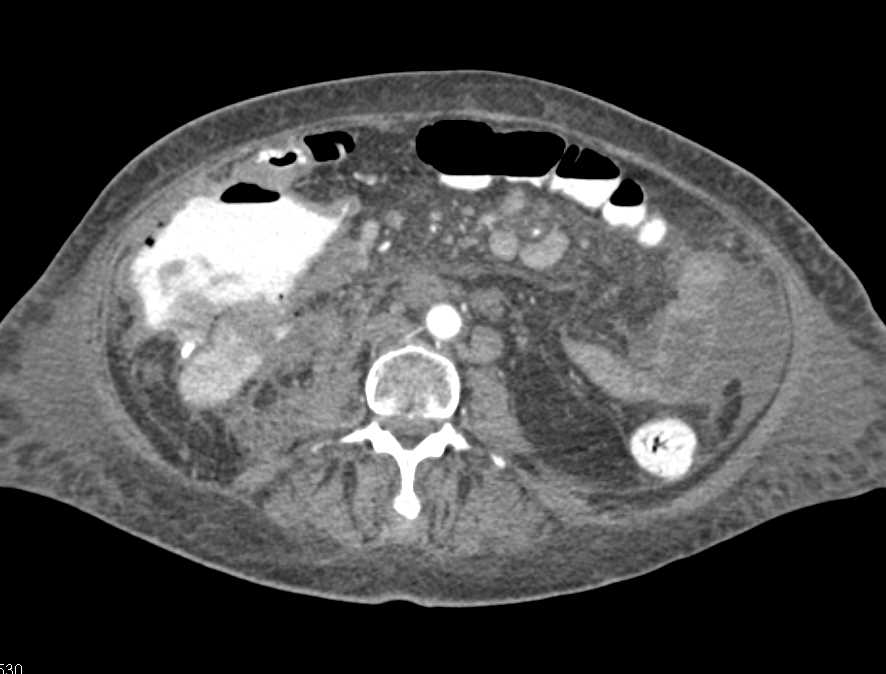

Ulcerating Cecal Carcinoma